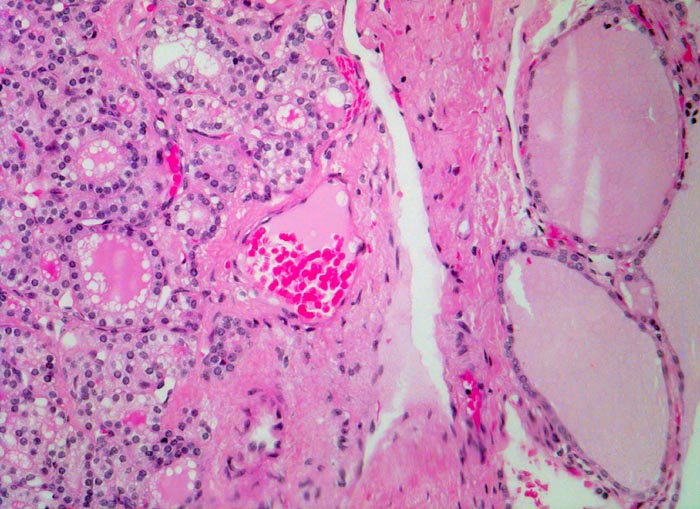

PathoPic – image database / PathoPic ID 4837 - autonomes Adenom

autonomes Adenom

Schilddrüse

Das Gewebe des Adenoms (links) ist verschieden vom Gewebe der angrenzenden Schilddrüse (rechts), aber mühelos als Schilddrüsengewebe identifizierbar. Der Knoten ist von einer Kapsel umgeben und dadurch scharf von der Umgebung abgegrenzt. Die Follikel im Adenom sind deutlich kleiner. Die Lumina sind klein oder gar nicht nachweisbar. Das Kolloid weist zahlreiche Resorptionsvakuolen auf. Das übrige Schilddrüsenparenchym ist makrofollikulär. Die Follikel sind mit Kolloid gefüllt. Resorptionsvakuolen sind nicht erkennbar. Das Epithel ist abgeflacht.